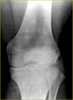

Osteopoikilosis

Osteopoikilosis is a benign, autosomal dominant sclerosing dysplasia of bone characterized by the presence of numerous bone islands in the skeleton. Presentation The radiographic appearance of osteopoikilosis on an X-ray is characterized by a pattern of numerous white densities of similar size spread throughout all the bones. [Source: Wikipedia ]